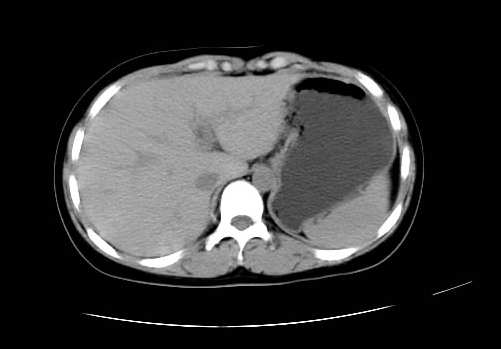

女 16岁  右上腹痛一天,无其他不适

肿块最大径位于十二指肠降段与水平段移行处,并且与肝脏压迹呈“0”形征,可以考虑位于肝外并与胃肠道关系紧密,考虑胃肠道间质瘤(gist)可能较大,须除外神经节起源肿瘤。

肿块与十二指肠关系密切,支持间质瘤诊断.肝脏与结肠均为受压改变.

右下腹巨大肿快,密度不均匀,内见坏死低密度区,边界清楚,与周边胀器明显有分界,未见强化,多考虑来源于间叶组织的良性肿物.

病灶巨大,少部分向肠腔内生长,大部分向长腔外生长。其密度不均匀,增强显示明显不均匀强化,并见有大片状始终不强化的不规则坏死液化区。虽然病灶中上部形态尚可,病人又如此年轻,但中下部形态、密度、强化特点强烈提示为恶性病灶。综上,我考虑本病例为:恶性胃肠道间质瘤。